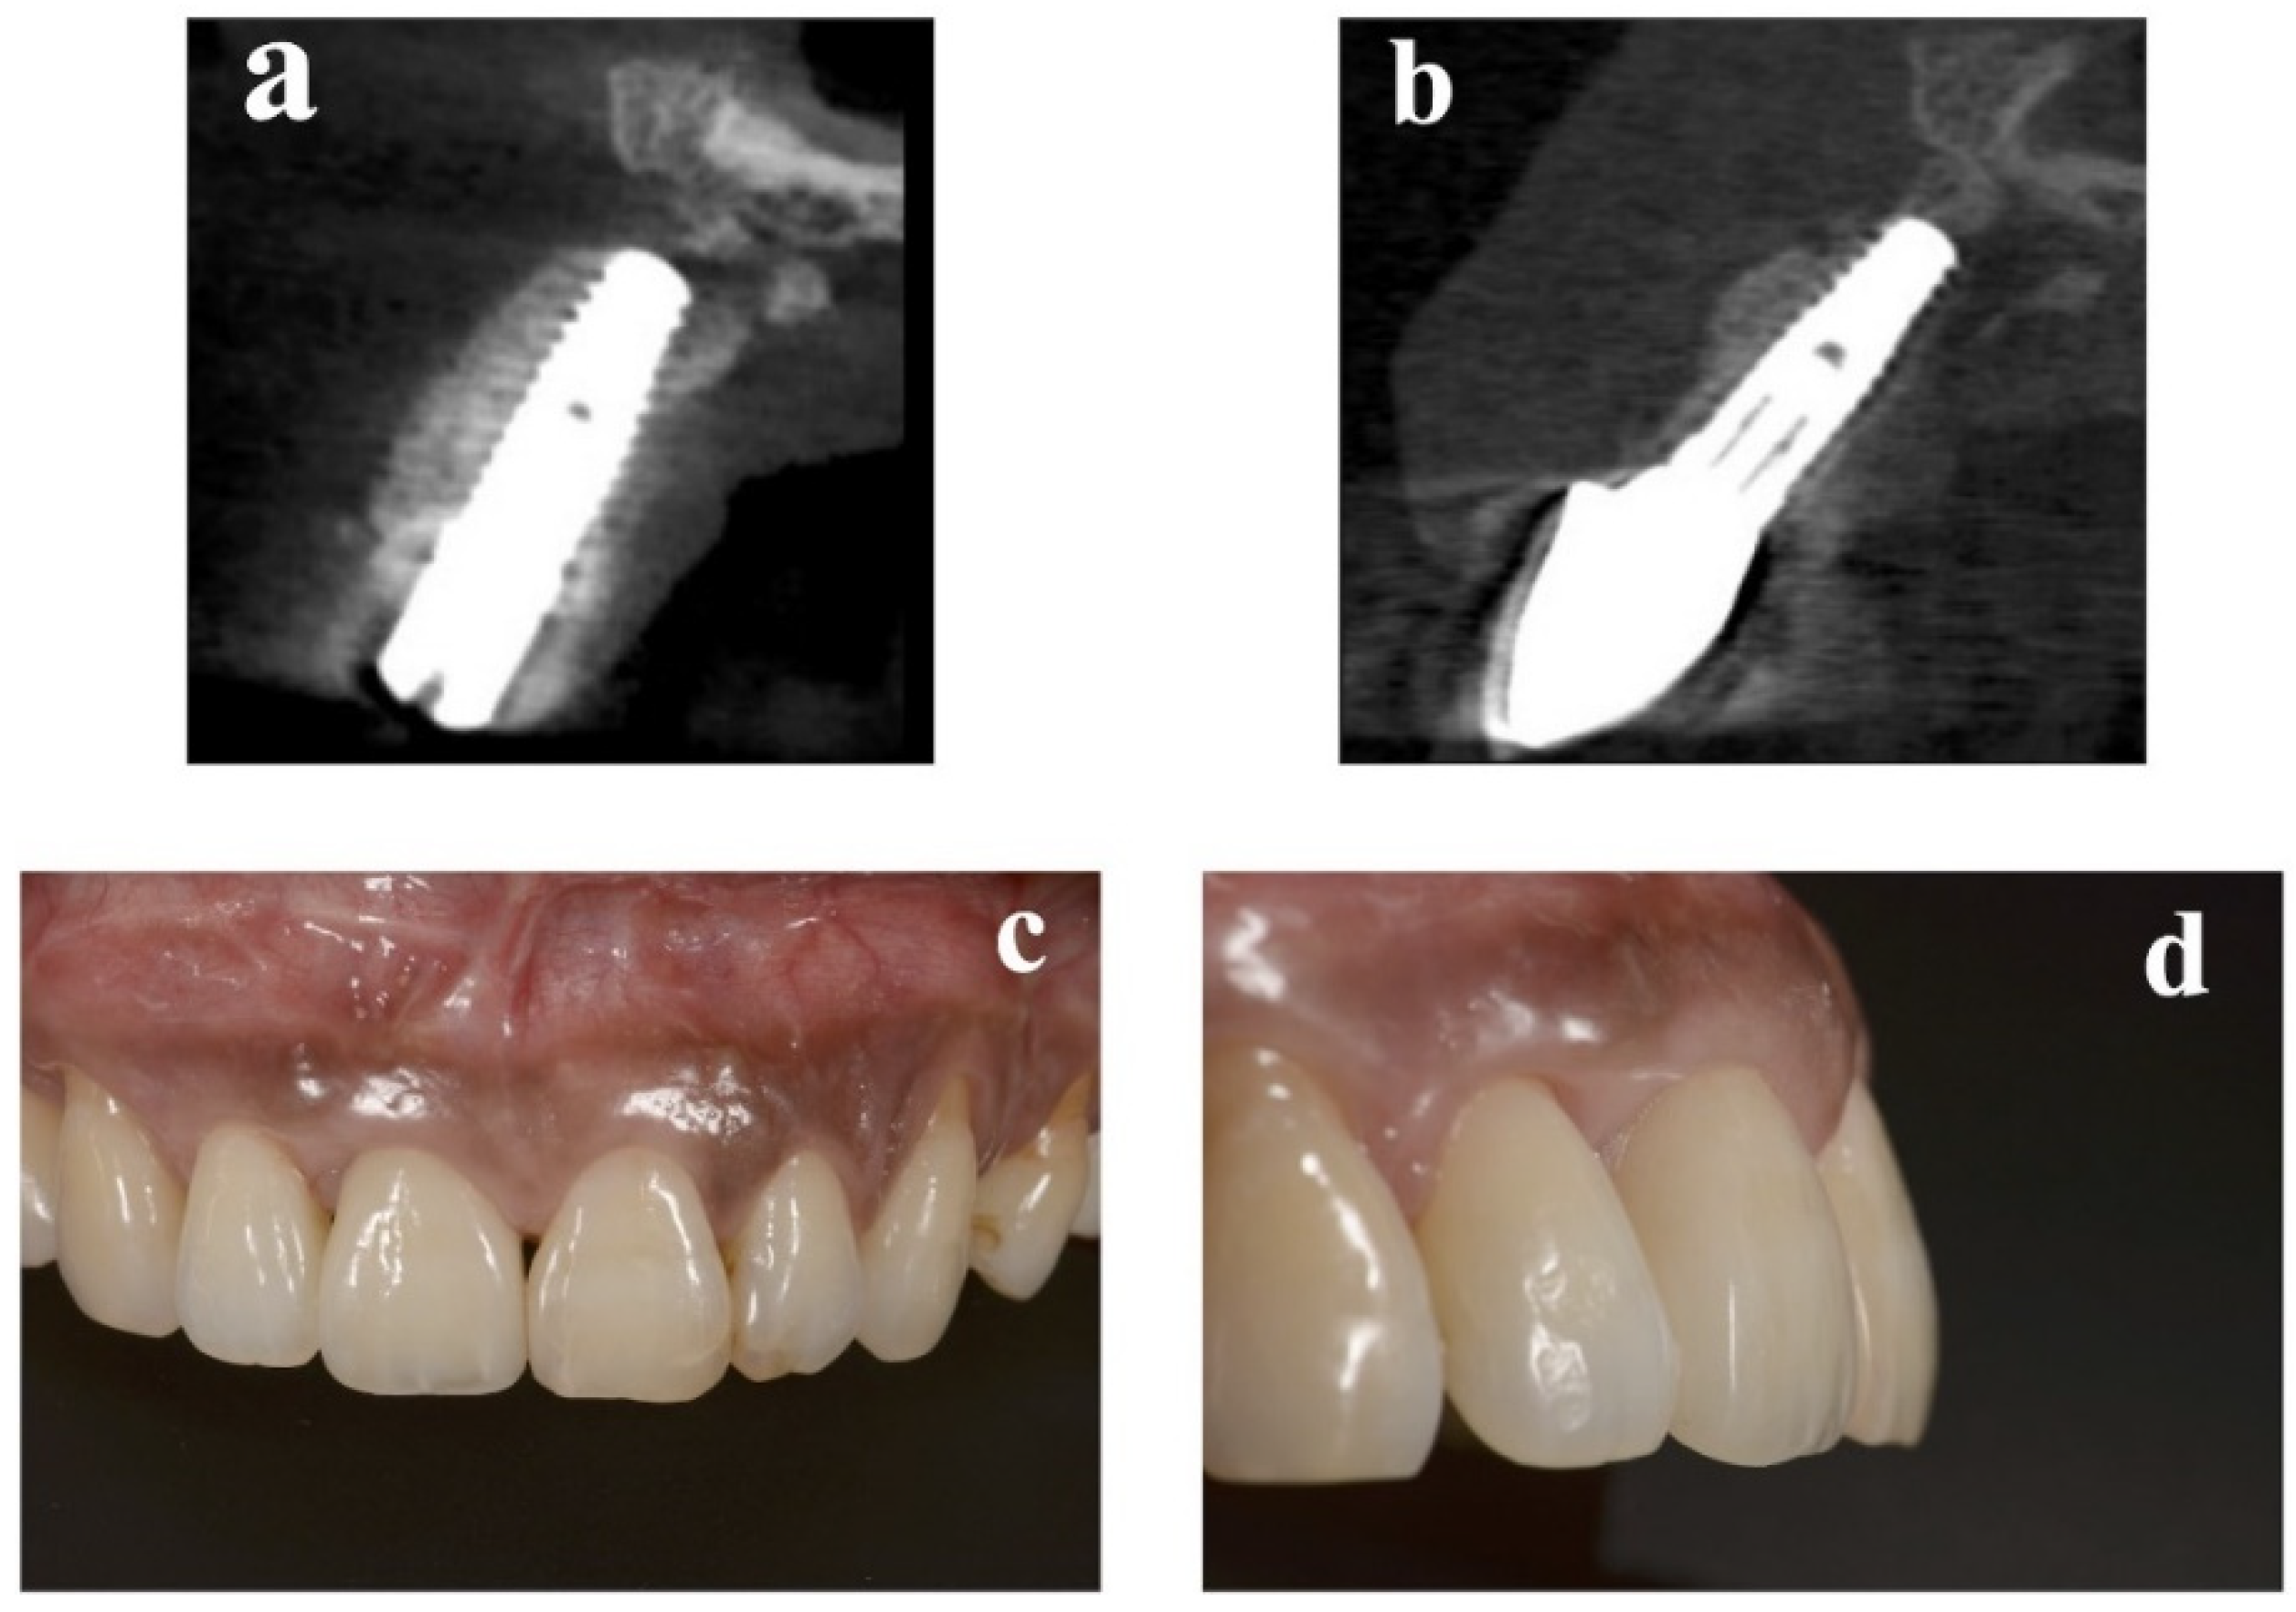

At the implant placement, the average augmented bone width was 2.8 ± 0.6 mm in CBCT analysis. In all cases, an average augmented bone resorption of −1.3 ± 0.8 mm was confirmed. CBCT images of immediate case #2 at implant placement and permanent restoration are shown in Figure 4a,b, respectively.

2.4. Esthetic Evaluation

Figure 4. Replacement of a maxillary central incisor with an immediate implant in case #2. (a) CBCT at implant placement. (b) CBCT 1 year later. (c) Frontal view of the final implant restoration. (d) Buccal view of the final implant restoration. CBCT: cone-beam computed tomography.